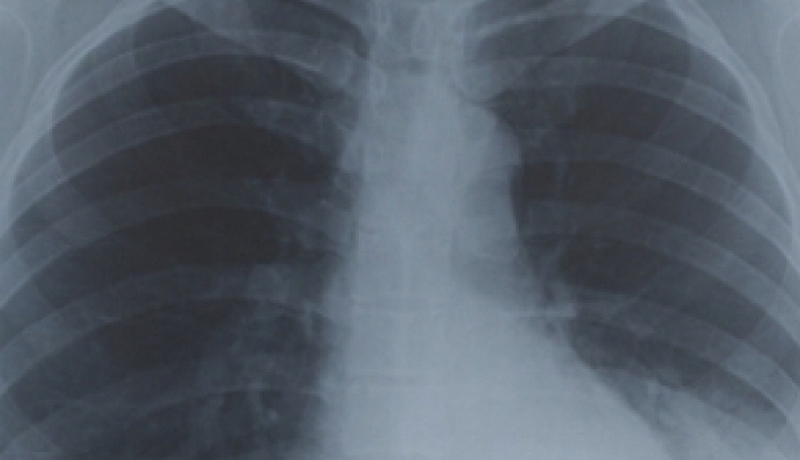

Radiografia pulmonară este esențială pentru diagnosticul, tratamentul şi monitorizarea bolnavilor cu afecțiuni respiratorii. Principalii beneficiari sunt persoanele incluse în Programul Național de Prevenire, Supraveghere și Control al Tuberculozei – contacți, suspecți sau bolnavi de TB – pentru care radiografia pulmonară este gratuită, precum și persoanele cu afecțiuni respiratorii nonTB, la cerere, acestea efectuând radiografia contra-cost. O radiografie pulmonară standard (film mic) cu interpretare costă 25 de lei, iar o radiografie fără film (pe CD) costă 20 de lei.